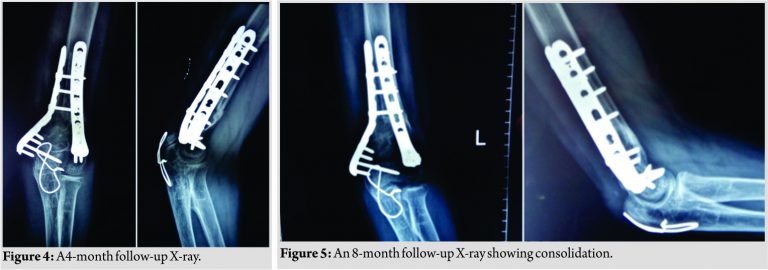

There was no donor site morbidity. Follow-up radiographs after 8 months showed full integration of fibular graft (Fig. 4 and 5).